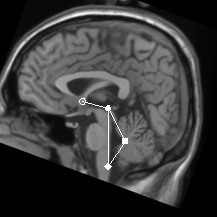

A line joining the PC and obex forms the basis for the proposed coordinate

system. The PC, obex and the apex of the fourth ventricle (V4) define the

cerebellar midplane. A transformed volume is created by rigid-body rotation

and translation (transform CB) that places the three principal

landmarks in the midplane and the PC-obex line in the same quasi-coronal plane

(Figure 1). A further one-dimensional rescaling (transform CBS)

![]() | Figure 1: Cerebellar midplane. The AC, PC, V4 apex and obex are marked. |